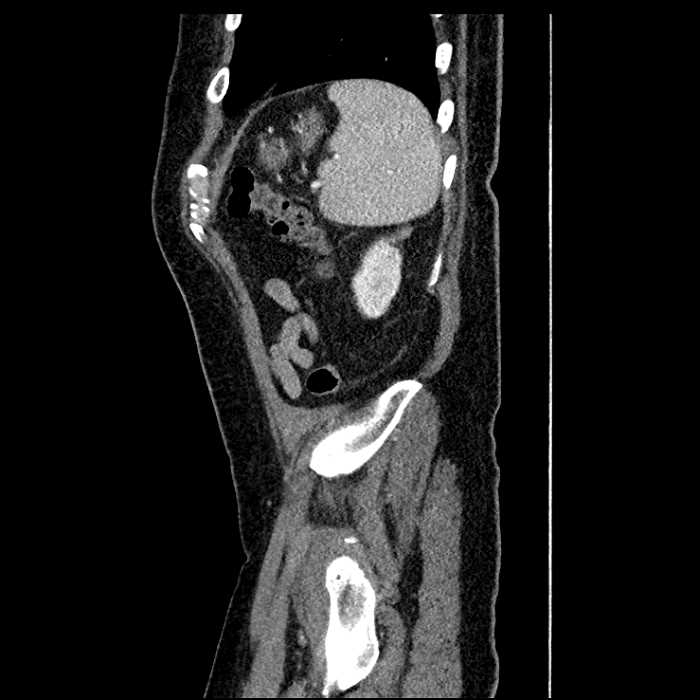

• Large fluid density structure in hepatic segments 7 and 8 measuring 10 x 7 x 7 cm with internal septation and circumferential ill-defined low density compatible with edema

Acute sigmoid diverticulitis complicated by a small contained perforation and a large abscess in the right hepatic lobe. Additional small subcapsular abscesses along the anterior margin of the left hepatic lobe.

Hepatic abscess showing the double target sign with low density internally surrounded by a thin inner enhancing rim (red arrow) and ill-defined outer low density rim (yellow arrow). Blue arrow indicates an internal septation. Red arrows: additional smaller subcapsular abscesses. Red arrow: focal contained perforation associated with diverticulitis.